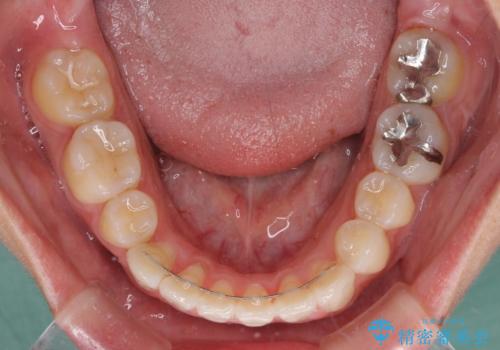

途中海外留学をされたため、治療期間は長くなりましたが、事前に補助装置やワイヤー装置を併用したことで、きれいな歯列に仕上げることができました。